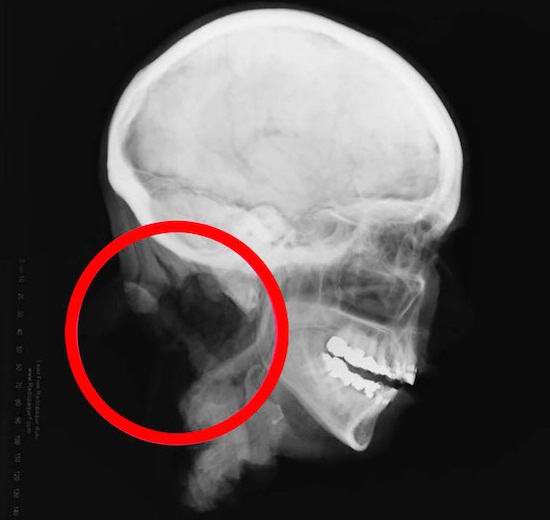

Odsek, ki je ločil glavo od telesa (kar še vedno ni mogoče najti) je bil spreten: izjemno gladek in natančen. Preostali vretenci lepo odstranjene iz vratne hrbtenice. To je preiskovalce spodbudilo k ideja, da je zločinec s profesionalcem kirurške veščine. Identificirati ženske ni bilo mogoče: niti odlitkov njenih zob, niti analize DNK, niti medijski portreti Jane Dow.

Nadalje – še bolj zanimivo in slabše. Želeli so forenzični strokovnjaki pregledati pokojnikove oči, vendar so presenečeni ugotovili, da je oftalmik v lobanji ni bilo jabolk. Namesto tega so v orbito vstavili rdeče. gumijaste kroglice s tankimi lečami. Najprej so se pojavili specialci različica, da so bile oči odstranjene za namene darovalca, vendar je povzročil dvom. Zakaj bi potem zamenjali oči s takimi “kozmetičnimi proteze “? Zdelo se je, da je skrivnostni zločinec želel to glavo obdržati kot eksponat ali okras. Lokalni zdravniki še nikoli niso videli česa takega.